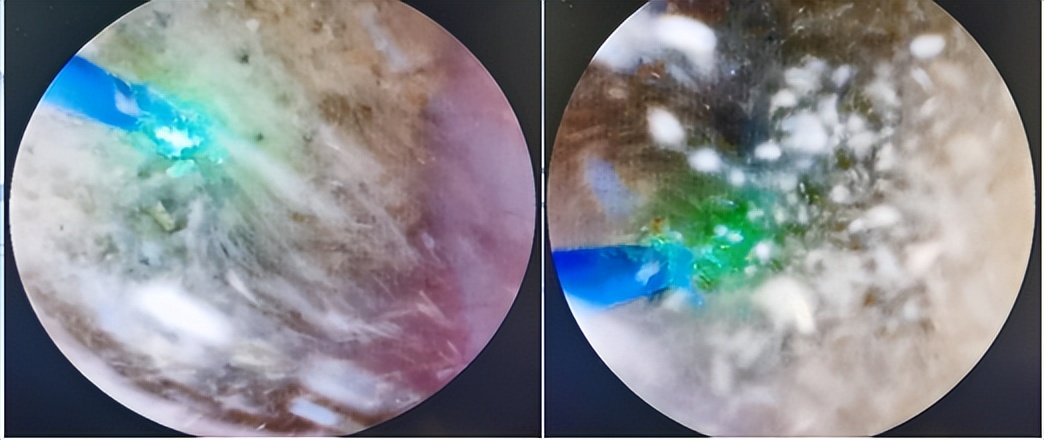

石仔,输尿管软镜漂洋过海只为你,经皮肾镜翻山越岭来看你。石为知己者死。输尿管软镜和经皮肾镜是伺候肾结石的绝代双骄。但凡内腔镜碎石,无论输尿管软镜、经皮肾镜,皆按部就班:(镜子)进了、(激光)射了、(结石)出来了。镜程所至,金石为开。大石化小,小石化了,碎石万段,碎碎平安。

输尿管镜倚仗钬激光光复石地。结石惹钬上身,石亡钬(激光)击。钬激光光纤与软镜虽然一个鼻孔出气,但寄人篱下的光纤却有锐气很任性,刚愎自负,我行我素。软镜内卷光纤不举,软镜躺平光纤出头;软镜光纤常互相拖后腿,导致结石可望而不可击。软镜与光纤需要磨合,方可比翼双飞、治石至终。

石物的品相取决于钬激光的火候。对于质硬、体积较小的结石,推荐高能、低频、短脉宽钬激光碎石模式(钬激光设置通常在0.6-1.0 J和6-10 Hz之间),使结石碎块化成肉丁;对于质软的结石,可以采用低能、高频、长脉宽的模式(0.2–0.6 J和20–80 Hz),只要功夫深,铁石磨成粉。